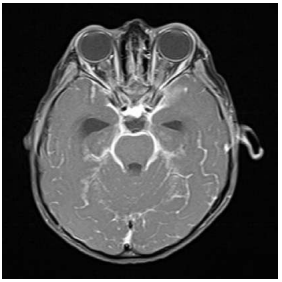

Considere-se a imagem a seguir.

Foi realizado eletrocardiograma do paciente e solicitada troponina. Com base no quadro clínico e na imagem apresentada, assinale a opção que apresenta a conduta adequada.